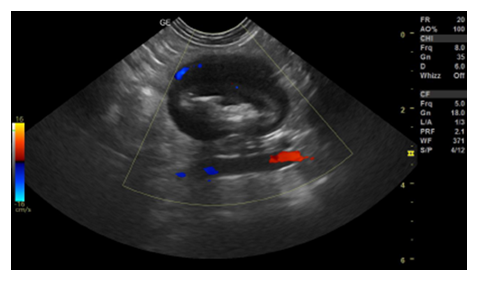

After the clinical examination, a complete blood count, serum biochemistry, urinalysis, abdominal ultrasound and electrocardiogram were requested. The blood count, as well as serum biochemistry tests, showed values within the normal range for the species. Abdominal ultrasound identified the presence of a mass in the left mesogastric region in the jejunal segment that was not causing luminal obstruction (Figure 1).

Figure 1: Abdominal ultrasound. Presence of a focal area with a segment measuring approximately 3.17 cm × 2.31 cm in the jejunum, without lumen obstruction, wall measuring approximately 1.05 cm, presenting an evident muscular layer in the ventral portion, filled with food and gaseous content with discreet vascularization on Doppler.